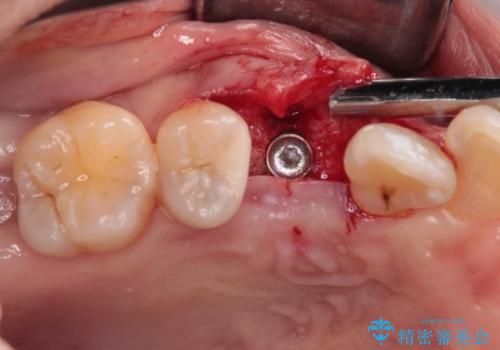

2本の歯が前後に重なった状態でむし歯となっていたので、抜歯後に歯肉や骨の状態が落ち着くのを待ち、インプラントを埋入することとしました。

崩壊した歯は全て抜去し、他人から見える位置の歯はセラミッククラウンが装着され、整った口腔環境となりました。